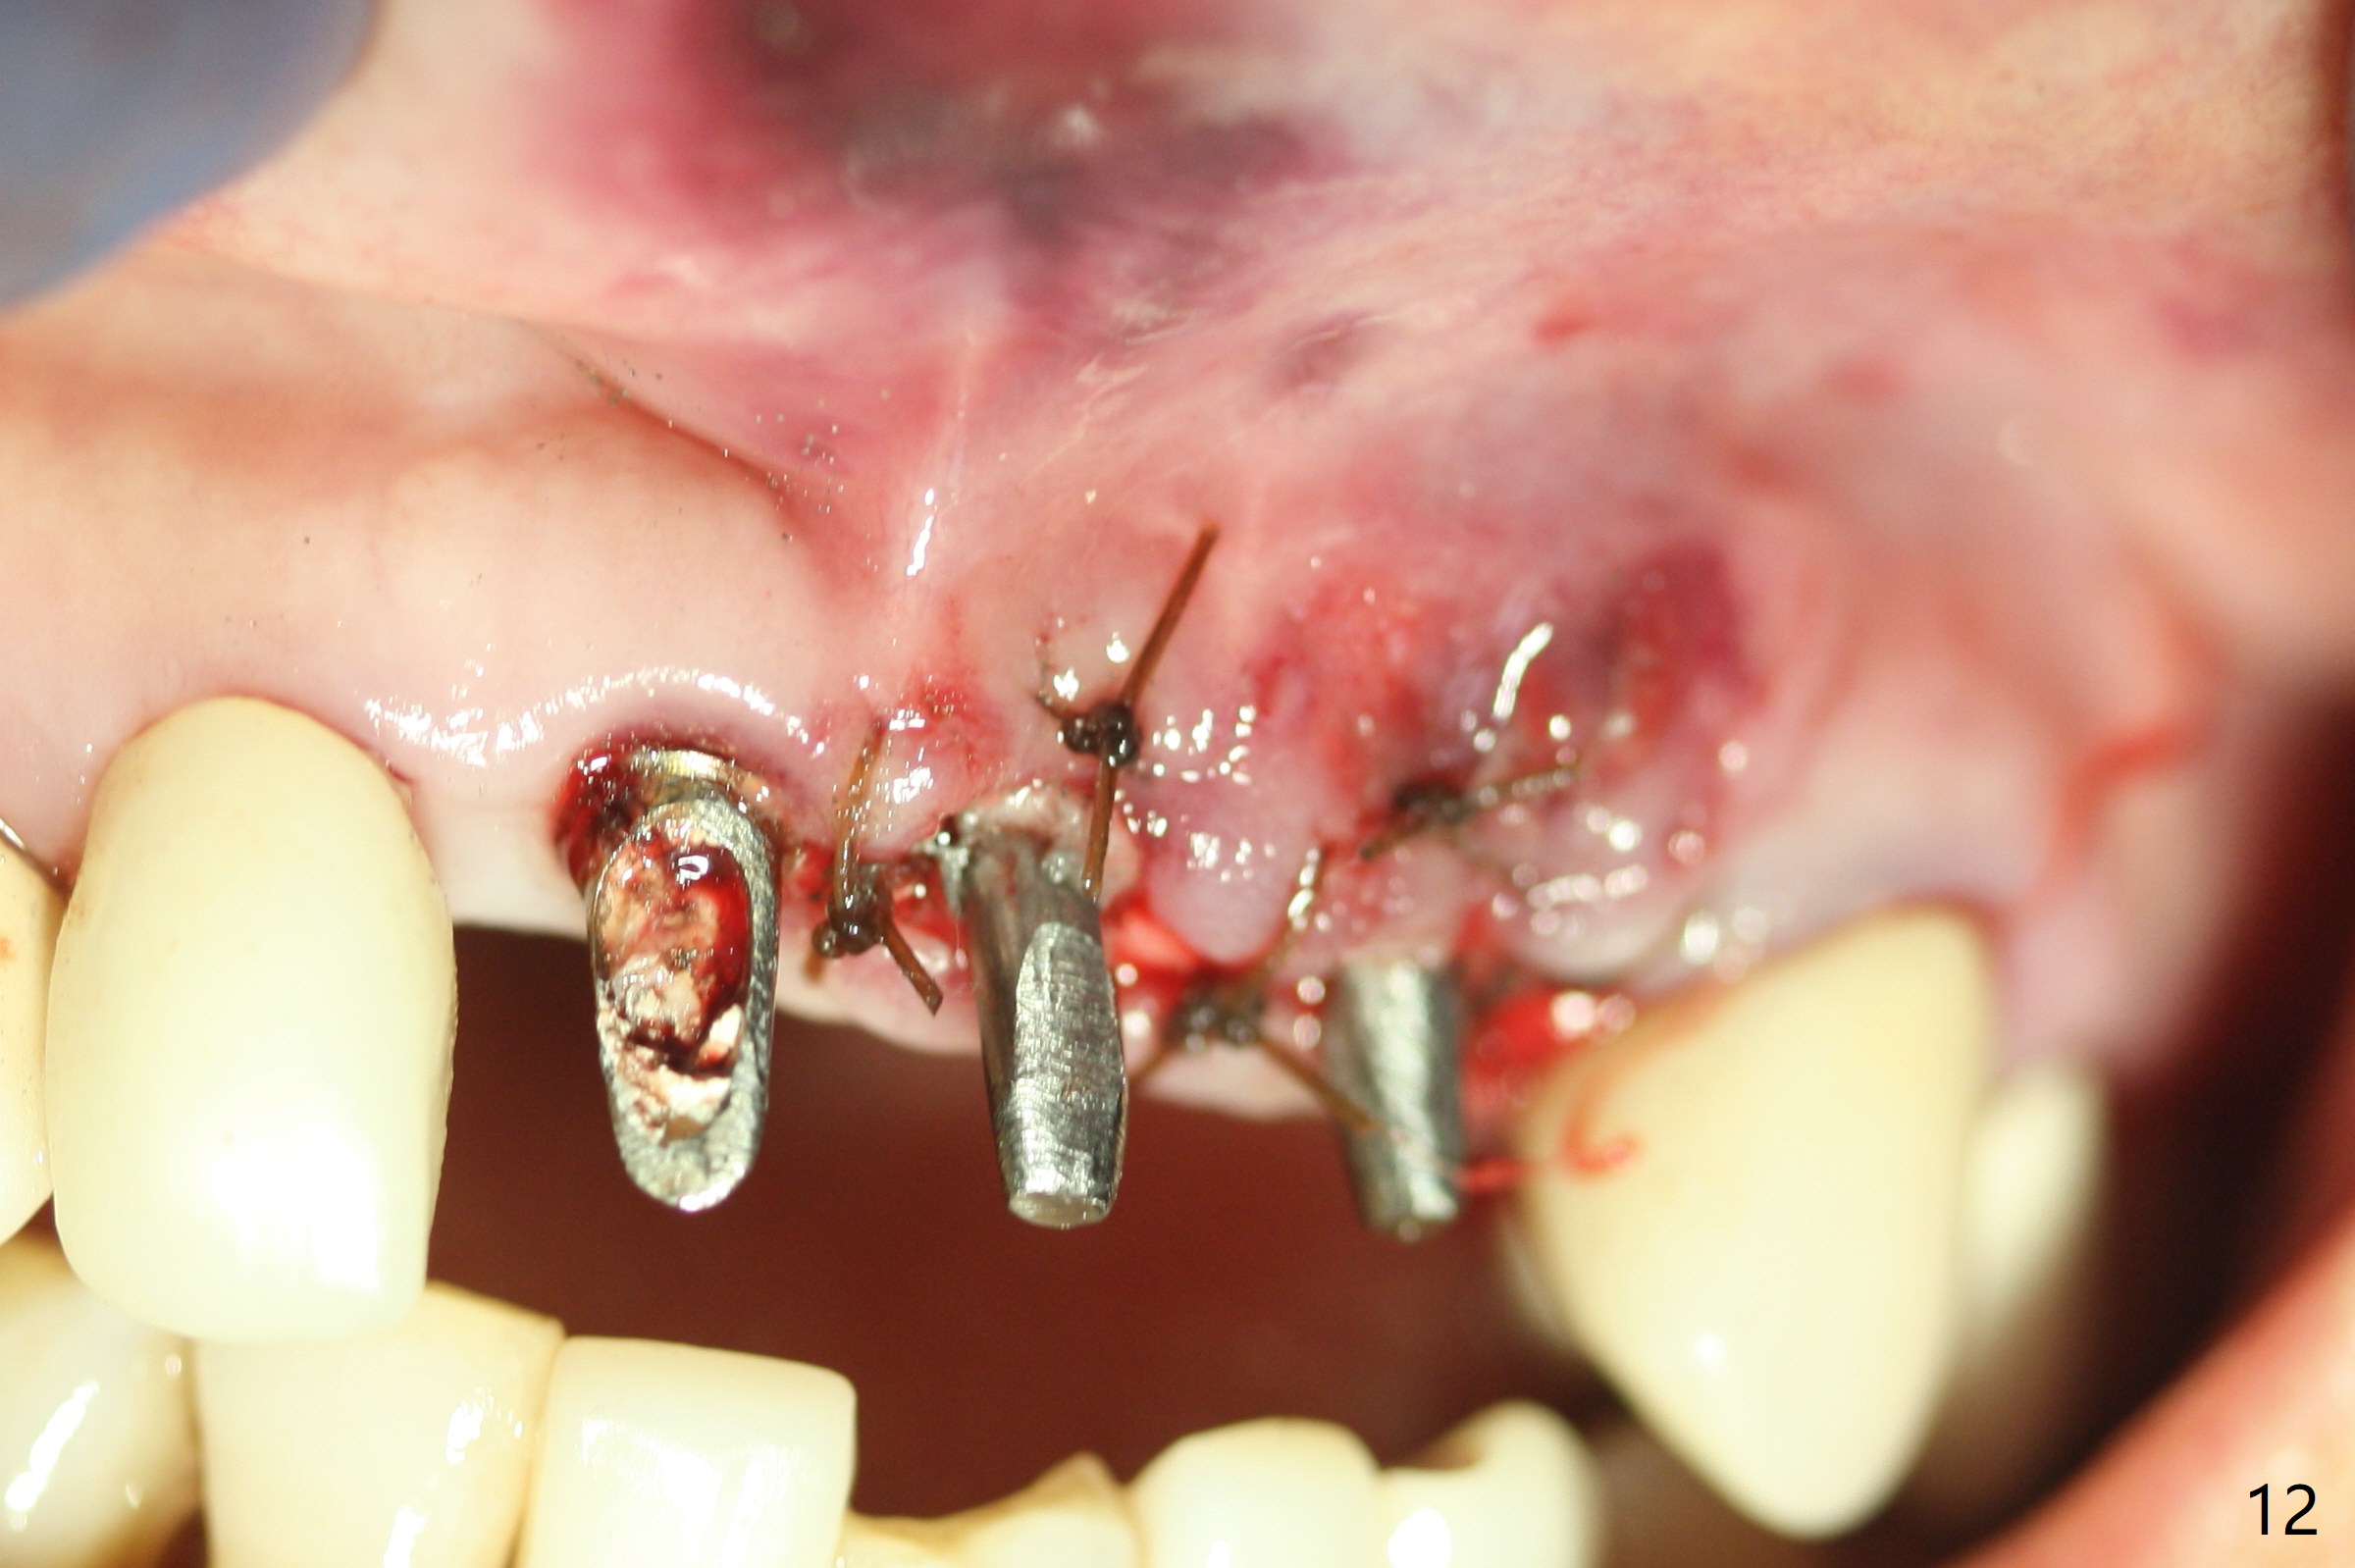

M

Incision shows exposure of microthreads at #9 and major threads at #10 due to buccal placement (Fig.1). There is bone palatal to the implant at #10 (Fig.2 P), to which a new implant will move. After implant removal, a narrower 1-piece implant (2.5x14(4) mm) is placed palatally at #10 (Fig.3,4) in combination of guide and free hand. At the site of #9 after implant removal, the guide is not used; a 3x17 mm angled 1-piece implant is placed with bad trajectory (Fig.5,6). After re-adjustment (Fig.7), the implant is placed at the right orientation (Fig.8). It appears that the guide is helpful. Allograft is placed mainly buccally (Fig.9,10 *), followed by a piece of collagen membrane (Fig.11). After tension release, flaps are approximated (Fig.12). The buccal gingiva at #9 and 10 recede nearly 2 months postop (Fig.13). Less recession at #9 is associated with more inflammation (Fig.14). The margin of the provisional is adjusted for gingival margin down growth and easy self cleaning with Water Pik (Fig.15). One month later, the gingival inflammation reduces, while there is no obvious buccal collapse (Fig.16,17). Impression is taken after laser gingivectomy nearly 4 months postop (Fig.18). While the gingiva around the implant at #9 is inflamed (periimplantitis?), the gingival cuff at #10 is well formed 5.5 months postop immediately before cementation (Fig.19). The buccal concavity at #10 is minimal (Fig.20). The gingival inflammation at #9 will be hopefully resolved after cementation of the final restorations (Fig.21). There appears to be new bone formation around the coronal implant threads 5.5 months postop (immediately post cementation, Fig.22). The microthreads at #9 may be not covered by the bone, the reason for the gingival erythema. The redness at #10 is asymptomatic 5.5 months post cementation (Fig.23). 粘固后两年牙槽嵴骨质并没有再生(图二十四),说明第一术中植体必须植入骨下(基台部分要长,否则难于修复),第二牙槽嵴处不应该有压力,植入2.5毫米植体,最后钻头应该是2.5毫米,骨下1-3毫米(尝试项目)。